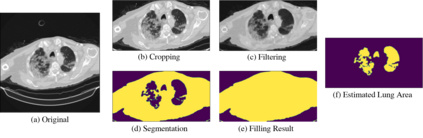

Computed tomography (CT) imaging could be very practical for diagnosing various diseases. However, the nature of the CT images is even more diverse since the resolution and number of the slices of a CT scan are determined by the machine and its settings. Conventional deep learning models are hard to tickle such diverse data since the essential requirement of the deep neural network is the consistent shape of the input data. In this paper, we propose a novel, effective, two-step-wise approach to tickle this issue for COVID-19 symptom classification thoroughly. First, the semantic feature embedding of each slice for a CT scan is extracted by conventional backbone networks. Then, we proposed a long short-term memory (LSTM) and Transformer-based sub-network to deal with temporal feature learning, leading to spatiotemporal feature representation learning. In this fashion, the proposed two-step LSTM model could prevent overfitting, as well as increase performance. Comprehensive experiments reveal that the proposed two-step method not only shows excellent performance but also could be compensated for each other. More specifically, the two-step LSTM model has a lower false-negative rate, while the 2-step Swin model has a lower false-positive rate. In summary, it is suggested that the model ensemble could be adopted for more stable and promising performance in real-world applications.